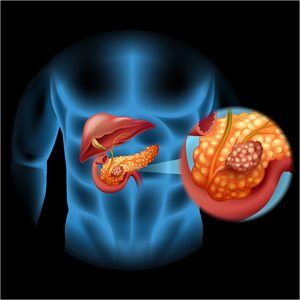

Aizkuņģa dziedzera vēzis

Izolīšu šūnu karcinoma